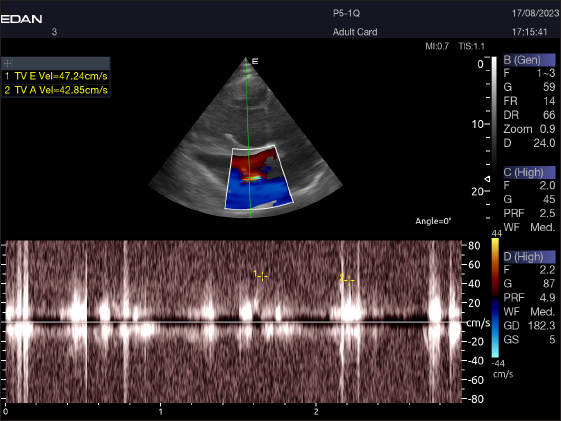

Left parasternal ultrasonography

The Mv E/A (Fig. 8), Tv E/A (Fig. 9), and maximum velocity of the aortic valve (Av Vmax) (Fig. 10) were all measured using pulsed-wave Doppler at LPSLAx in all camels. Two cases were observed with mild mitral regurgitation detected through continuous-wave Doppler, but the regurgitation was not considered significant (Fig. 11).

Fig. 9. Left parasternal longitudinal axis of an 18-year-old racing camel showing pulsed wave Doppler over the tricuspid valve (1=E wave and 2=A wave).